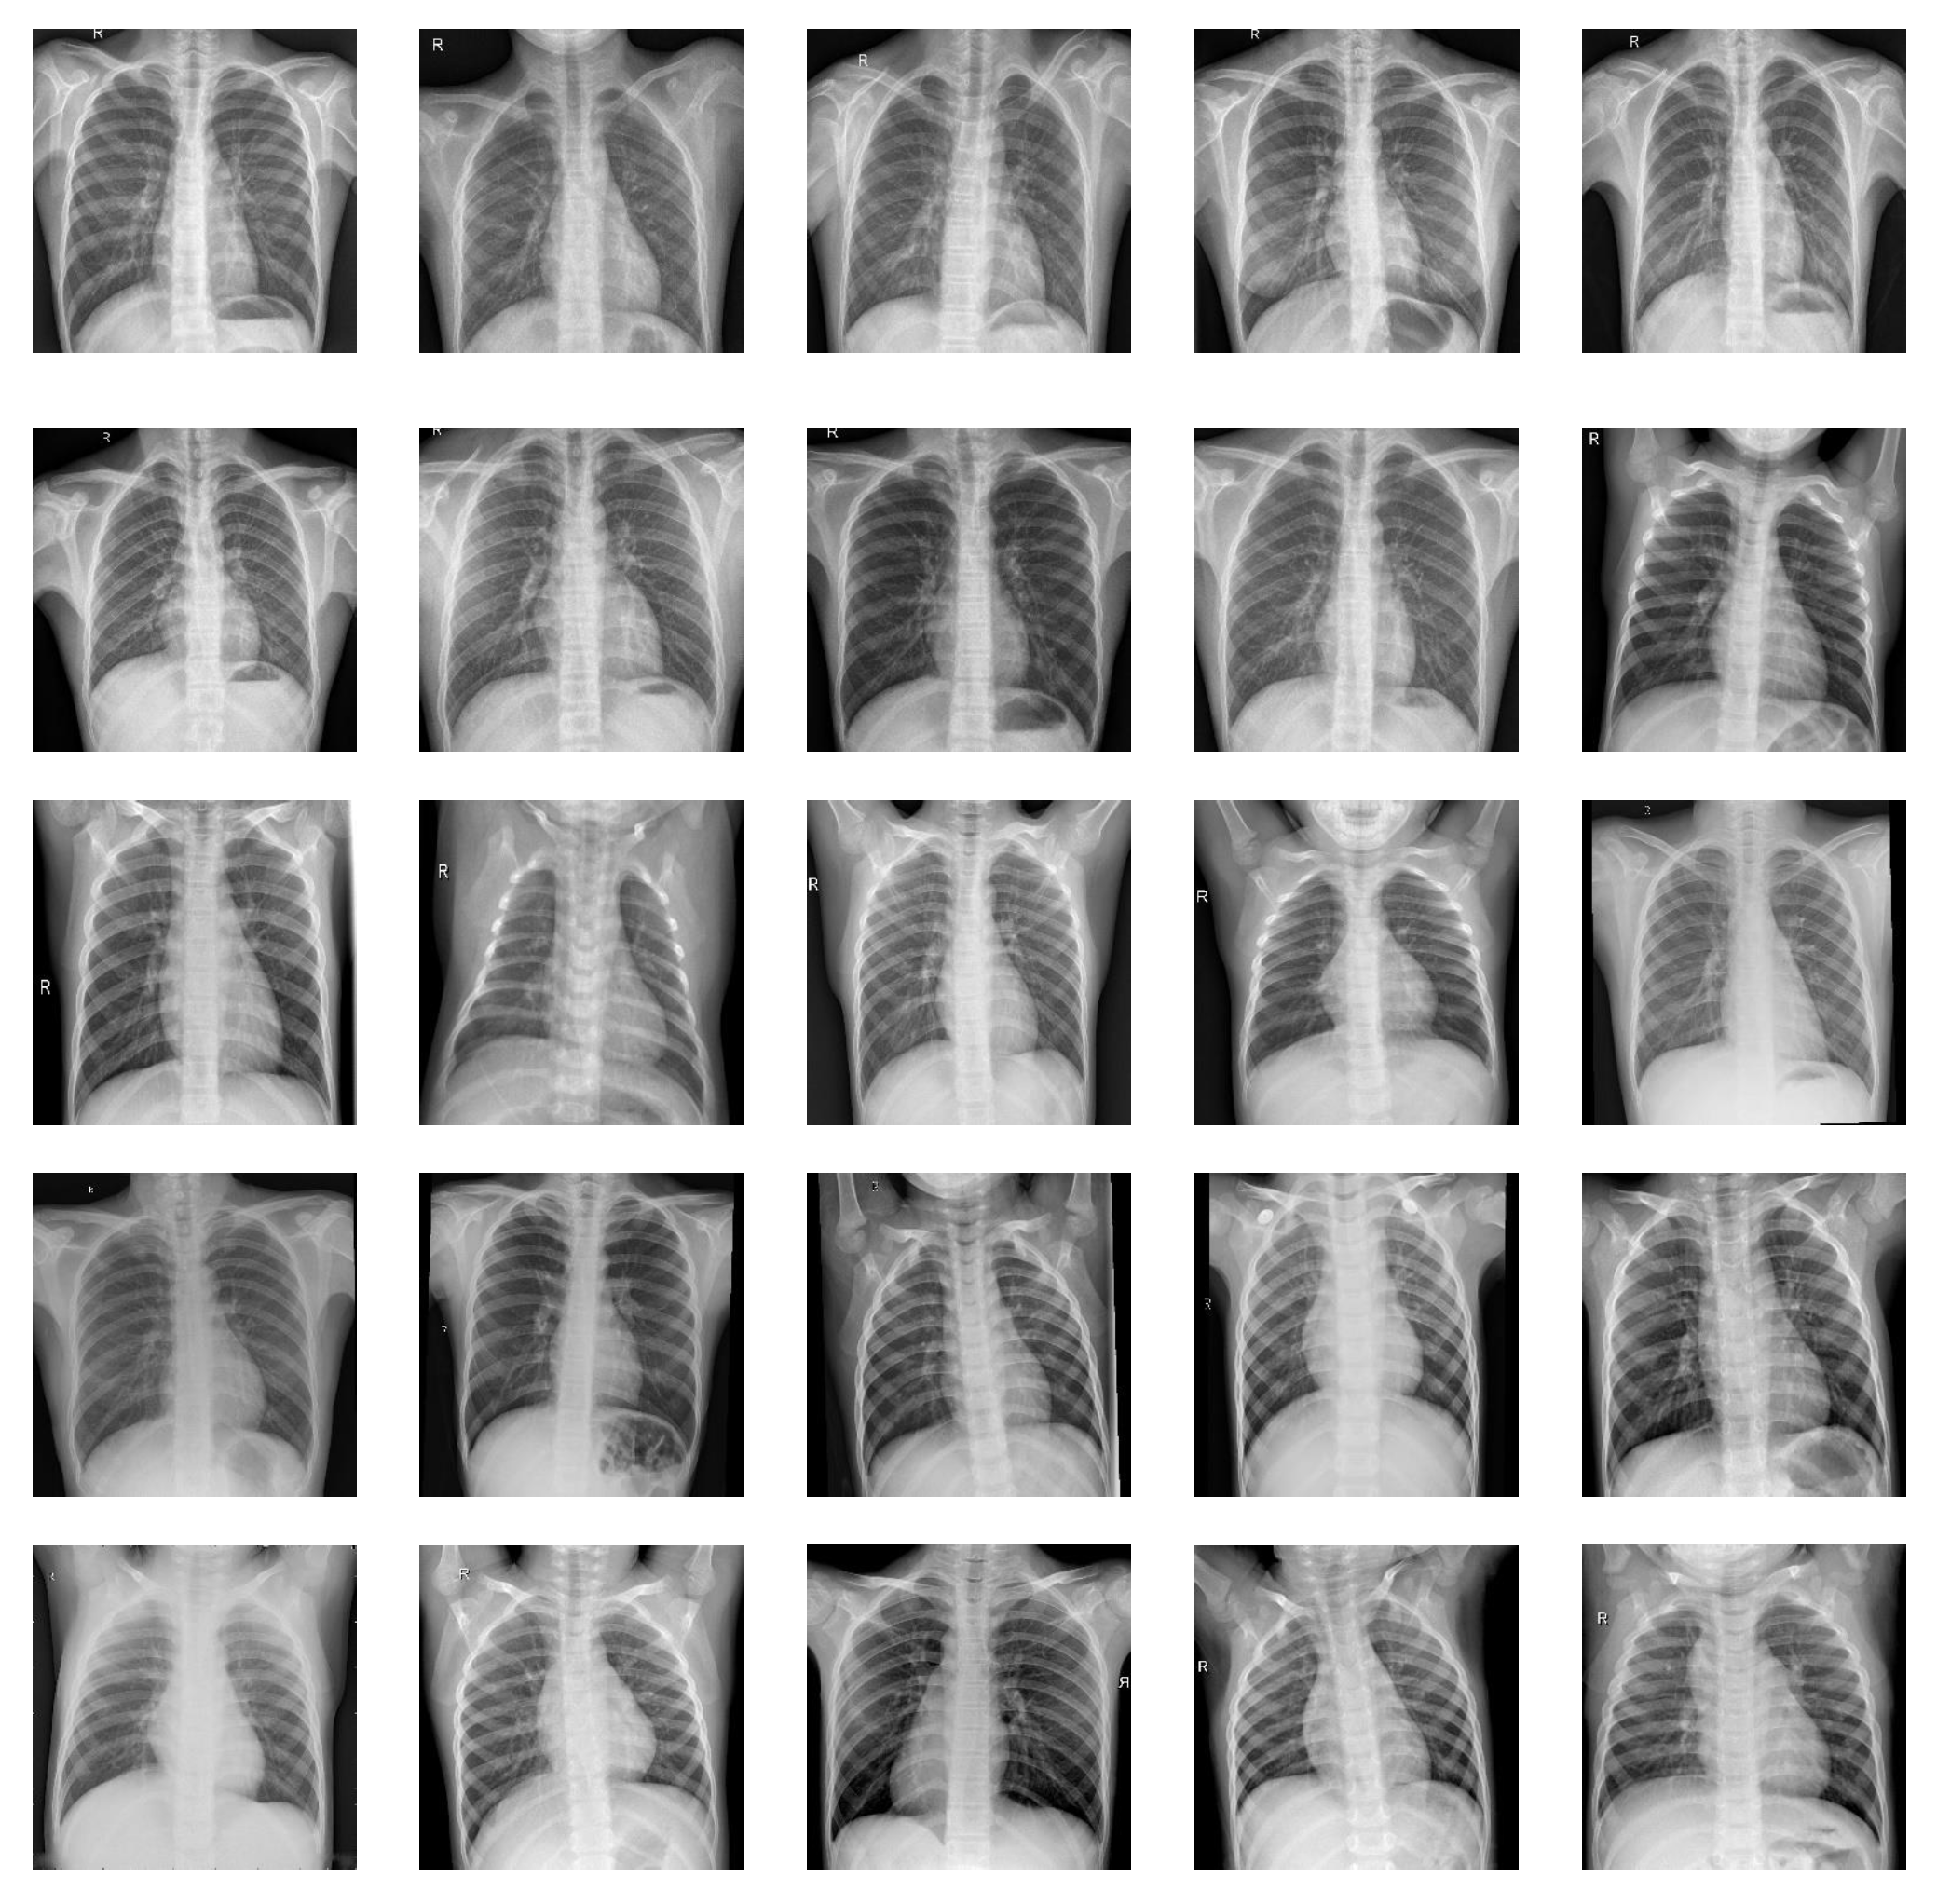

2.2. Step 1: Data Collection and Cleaning

2.2.1. Data Collection and Processing

| Pneumonia | 1575 X-ray images | Training set (80% randomly selected) | 1260 X-ray images |

| Testing set (20% randomly selected) | 315 X-ray images | ||

| Normal | 1575 X-ray images | Training set (80% randomly selected) | 1260 X-ray images |

| Testing set (20% randomly selected) | 315 X-ray images |